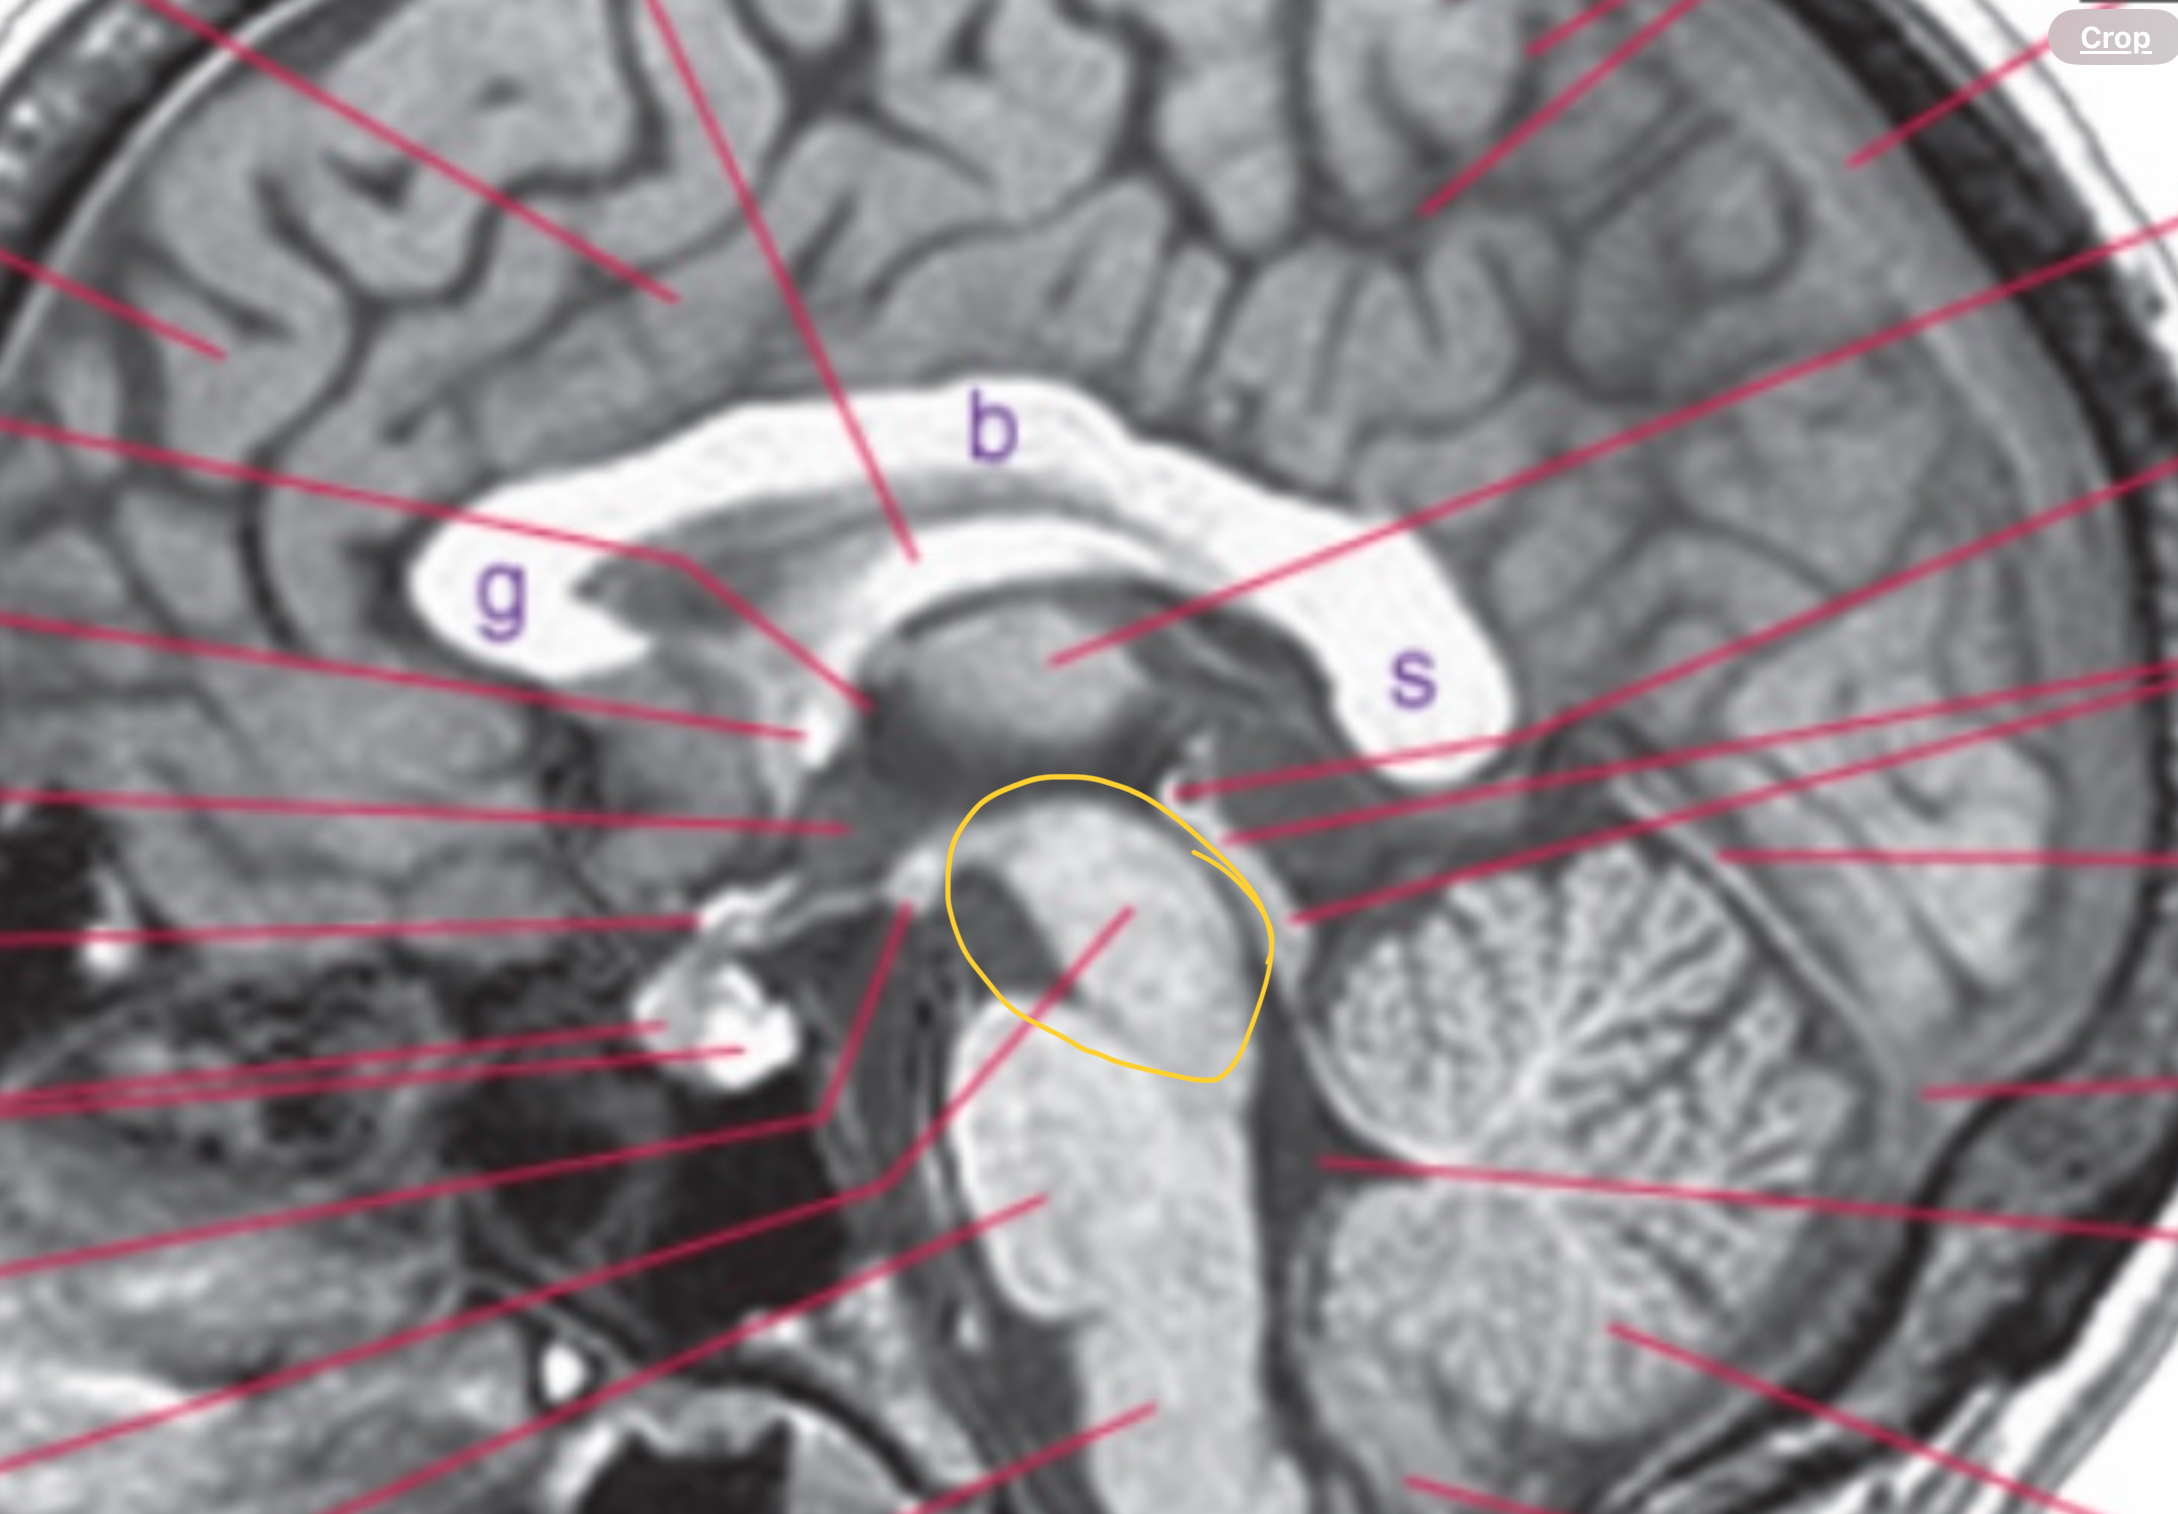

Obex

Where 4th ventricle becomes continuous with central canal

“V” where the vent becomes central canal